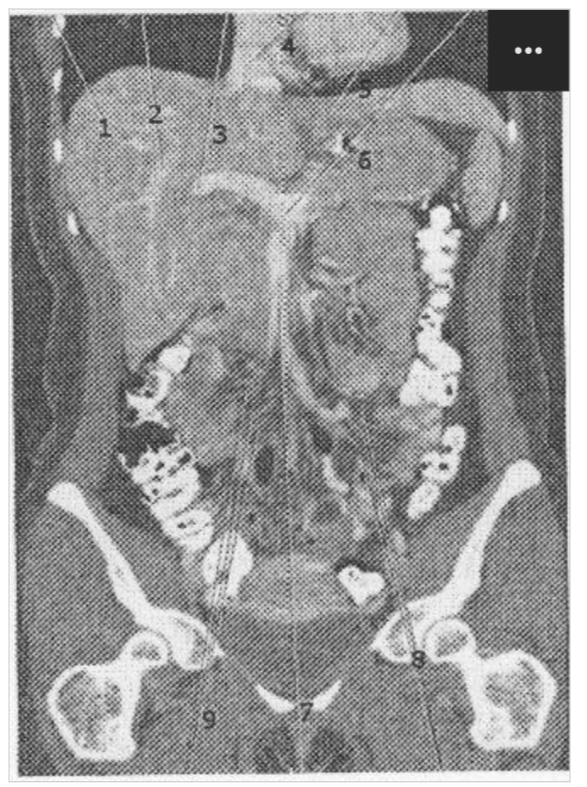

1 Which of the following represents the left lobe of the liver?

2 Which represents the right main portal vein?